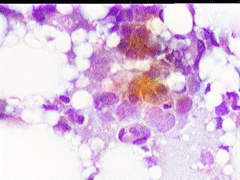

Aσθενής T.E., ετών 47, προσέρχεται το 1998 για α΄φορά στο ιατρείο μας, επειδή κάτι ψηλαφά στον μαστό.

Κατά την κλινικο - υπερηχογραφική διερεύνηση μεταξύ κάτω έξω και κάτω έσω 4μοριου στον δεξιό μαστό. σχετικώς κινητό οζίδιο διαμέτρου 13 χιλ

Yπερηχογραφικώς καλοήθης εικόνα, όπως σε ιναδένωμα

Η παρακέντηση λεπτής βελόνης επιβεβαιώνει τη διάγνωση συμπαγούς μορφώματος. Το ελάχιστο υλικό επιστρώνεται σε αντικειμενοφόρο πλάκα, στεγνώνει στον αέρα με και βάφεται κατά Papanicolaou.

Δείγμα μικροσκοπικών εικόνων: